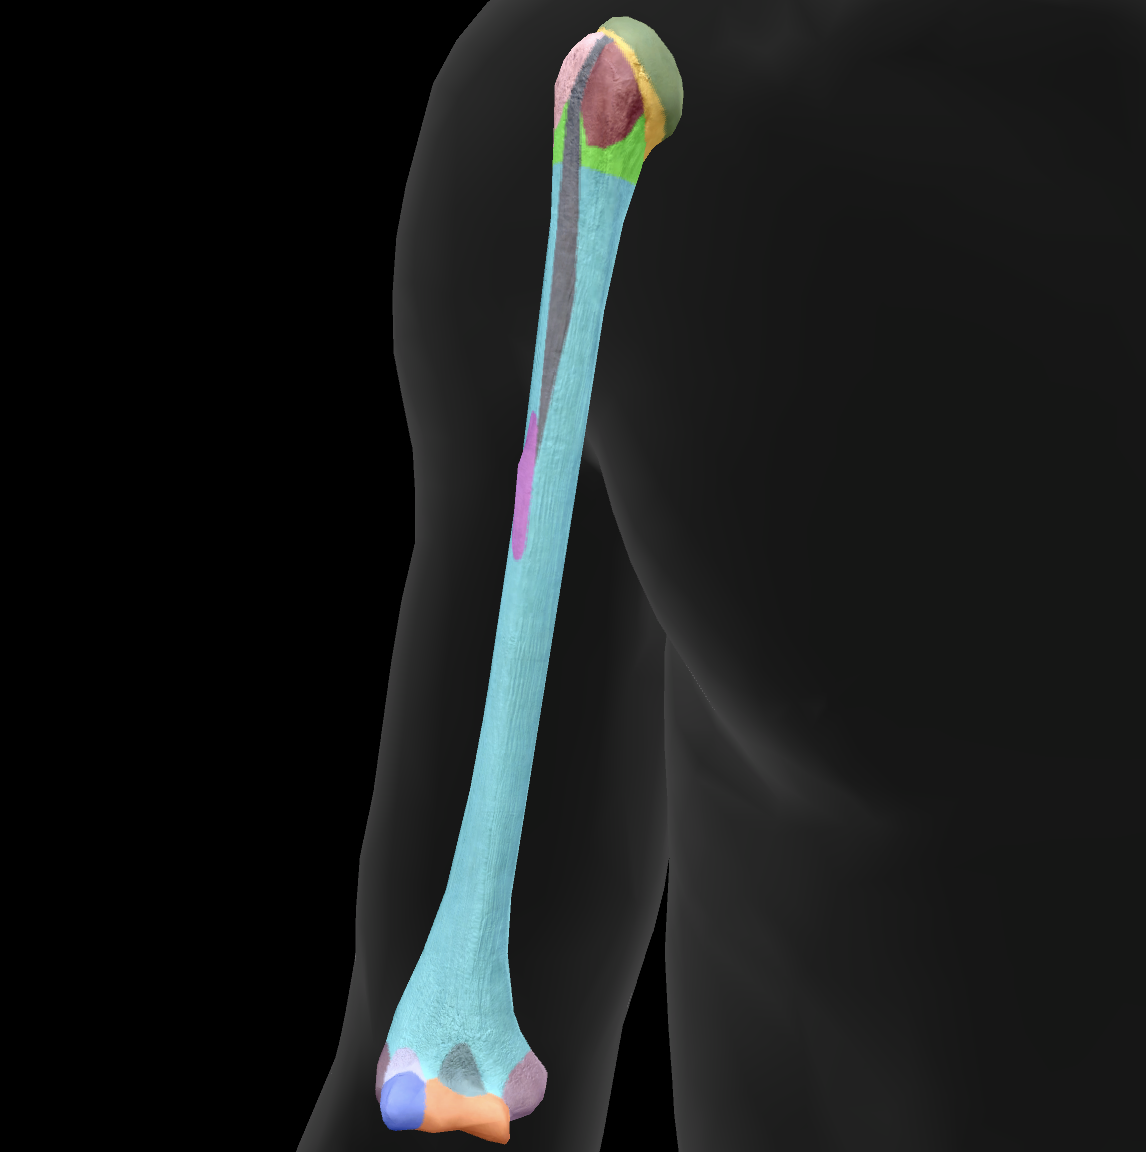

What bone is this?

humerus

What is this boney landmark?

head

What is this boney landmark?

anatomical neck

What is this boney landmark?

surgical neck

What is this boney landmark?

lesser tubercle

What is this boney landmark?

bicipital grove

What is this boney landmark?

deltoid tuberosity

What is this boney landmark?

shaft

What is this boney landmark?

capitulum

What is this boney landmark?

trochlea

What is this boney landmark?

radial fossa

What is this boney landmark?

coronoid fossa

What is this boney landmark?

medial epicondyle

What is this boney landmark?

lateral epicondyle

What is this boney landmark?

greater tubercle

What is this boney landmark?

radial grove

What is this boney landmark?

olecranon fossa

What is this boney landmark?

lateral supracondylar ridge

What is this boney landmark?

medial supracondylar ridge